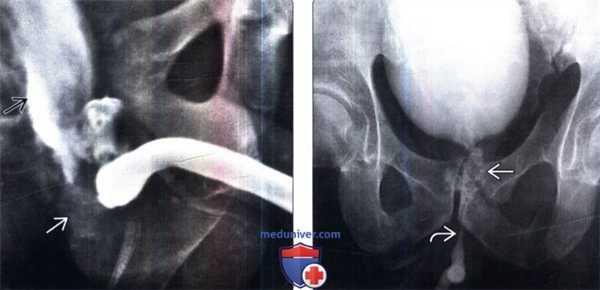

(Слева) На ретроградной уретрографии (РУГ) определяется растянутая, но не вовлеченная задняя уретра. Эти признаки характерны для 1 типа травмы по классификации Голдмана. Следуя классификации AAST, такие признаки характерны для 2 типа. Обратите внимание на диастаз лобкового симфиза.

(Справа) На РУГ определяется экстравазация контрастного вещества из задней уретры; обратите внимание на экстравазат контрастного вещества, расположенный в кверху от мочеполовой диафрагмы. Эти признаки характерны для травмы 2 типа по классификации Голдмана.

(Слева) На РУГ определяется травма 3 типа по классификации Голдмана с экстравазацией контрастного вещества кверху и книзу от уровня мочеполовой диафрагмы.

(Справа) На РУГ определяется экстравазация контрастного вещества из места разрыва шейки мочевого пузыря, которая распространяется до проксимального отдела уретры (травма 4 типа по Голдману). Обратите внимание на симметричную коническую форму проксимального отдела бульбарной уретры, который ограничивает место соединения передней и задней уретры, а также уровень мочеполовой диафрагмы.